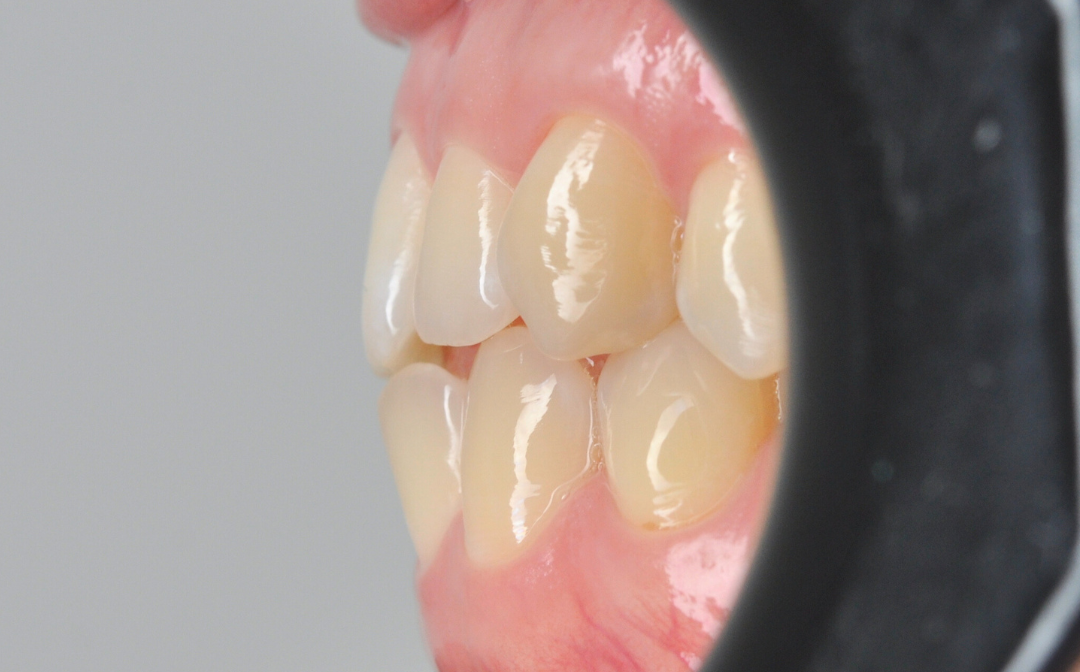

После

Этап №3

Ортодонтическая коррекция.

Стоматолог-ортодонт зафиксировал комбинированную брекет-систему (сверху керамические, а снизу – металлические брекеты).

- Исправление прямого прикуса (одной из частых причин дисфункции ВНЧС).

- Изменение положения зубов.

- Доведение контактов челюстей до физиологически правильного смыкания.